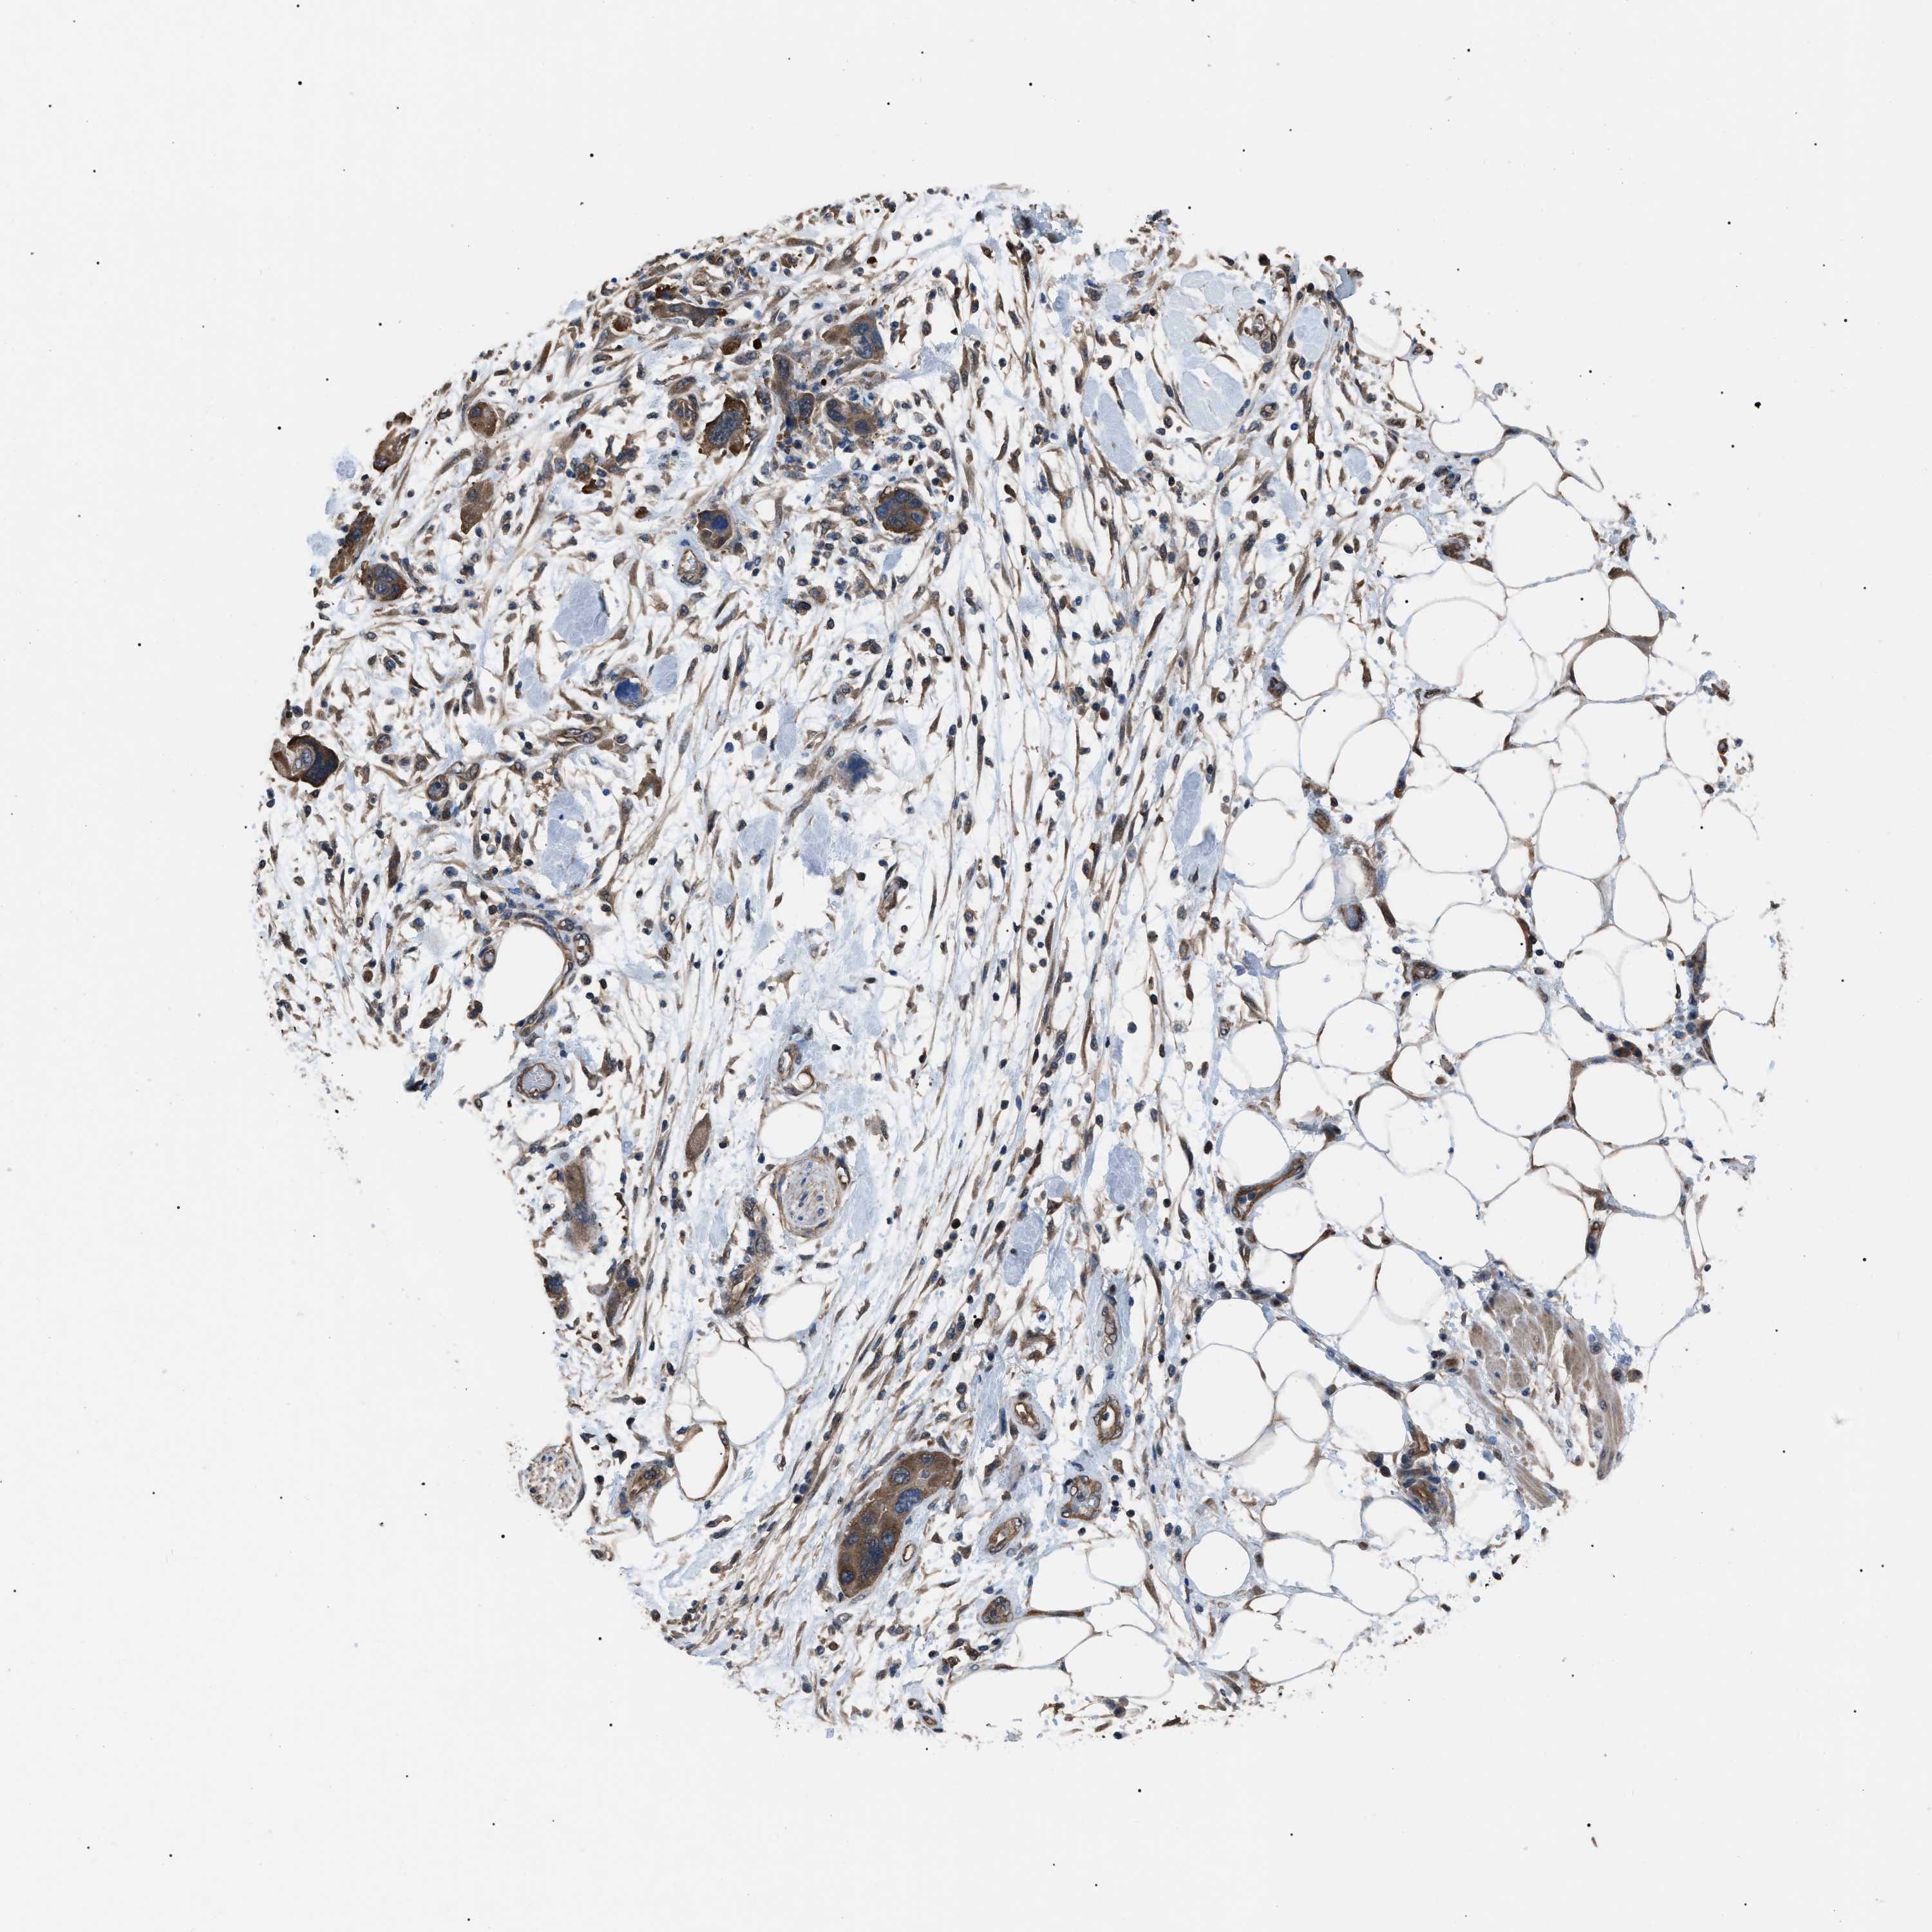

PANCREATIC CANCER - Protein expressioni

A mouse-over function shows sample information and annotation data. Click on an image to view it in a full screen mode. Samples can be filtered based on level of antibody staining by selecting one or several of the following categories: high, medium, low and not detected. The assay and annotation is described here.

Note that samples used for immunohistochemistry by the Human Protein Atlas do not correspond to samples in the TCGA dataset.

Antibody stainingi

Antibody staining in the annotated cell types in the current human tissue is reported as not detected, low, medium, or high, based on conventional immunohistochemistry profiling in selected tissues. This score is based on the combination of the staining intensity and fraction of stained cells.

Each image is clickable and will lead to virtual microscopy that enables deeper exploration of all samples and also displays staining intensity scores, fraction scores and subcellular localization as well as patient and tissue information for each sample.

Antibody HPA018471

Staining

High

Medium

Low

Not detected

Intensity

Strong

Moderate

Weak

Negative

Quantity

>75%

75%-25%

<25%

None

Location

Nuclear

Cytoplasmic/membranous

Cytoplasmic/membranous,nuclear

Adenocarcinoma, NOS